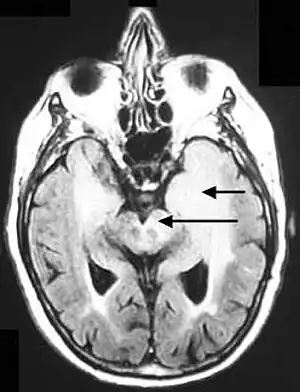

Axial fluid-attenuated inversion recovery MRI image demonstrating tumor-related infiltration involving both temporal lobes (Short arrow), and the substantia nigra (Long arrow).